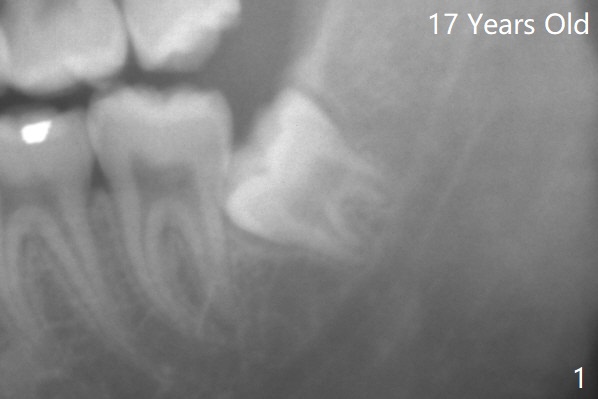

Multiple Sectioning     Last     Next   智齿拔除

Xin Wei, DDS, PhD, MS 1st edition 07/10/2021, last revision 07/18/2021